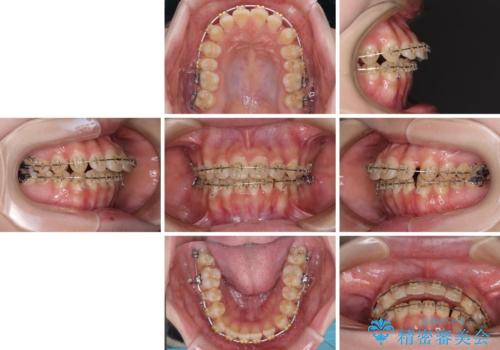

- 大学病院にて装置を装着したものの、治療が十分に受けることができないとのことで転院をされた患者様です。

上顎歯列が前方にあり、口元が閉じにくくなっていたため、既に装着されている装置を使用して上顎歯列全体を後方に移動させていくこととしました。

舌の突出癖があり、それが原因で上下前歯に隙間ができていたため、改善のためのトレーニングを行うように指示をしました。

舌の突出癖の影響か、なかなかスペースが閉じきらず、治療期間は予定よりも長期間となりました。

舌突出癖改善のトレーニングの重要性を認識することとなりました。